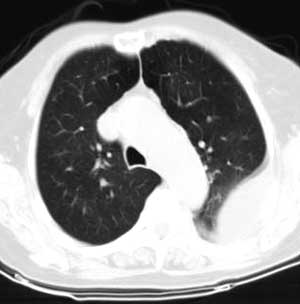

标题: CT0563:病历讨论,胸膜间皮瘤?

测ct值3-6hu,

既然ct值是3-6hu,还不如考虑包裹性积液。

请上传纵隔窗。目前还是支技包裹性积液(明显梭形),即使是间皮瘤并积液也少梭形的。

从图片看,包裹性积液好象更合理,梭形,ct值3-5hu(在哪看到的?);胸膜间皮瘤如此规则,不多见。

左侧背部胸膜肥厚,伴包裹性积液,不考虑间皮瘤.

同意以上各位的高见,首先考虑包裹性积液,1.胸膜间皮瘤积液量一般较大,以游离性积液更为常见,2.可以看到增厚的胸膜结节